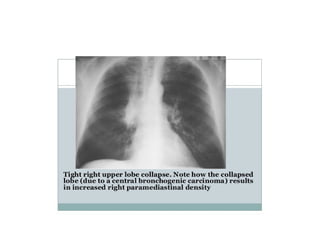

• RUL collapse

• Horizontal fissure displaced upward,The

upper half of oblique fissure moves

anteriorly.

• Hilum is elevated

• Tracheal deviation to right

• Compensatory hyperinflation of right

middle and lower lobes may be seen

RUL collapse

•

Golden‘s (reverse S)

sign. a. Chest X-ray of a

patient with a centrally

located mass. The

reverse S sign due to

right upper lobe

atelectasis is clearly

depicted. The lateral

portion of the ‘S’ is

formed by the superiorly

displaced minor fissure

and the medial portion by

the mass (arrows). b.

Golden S.